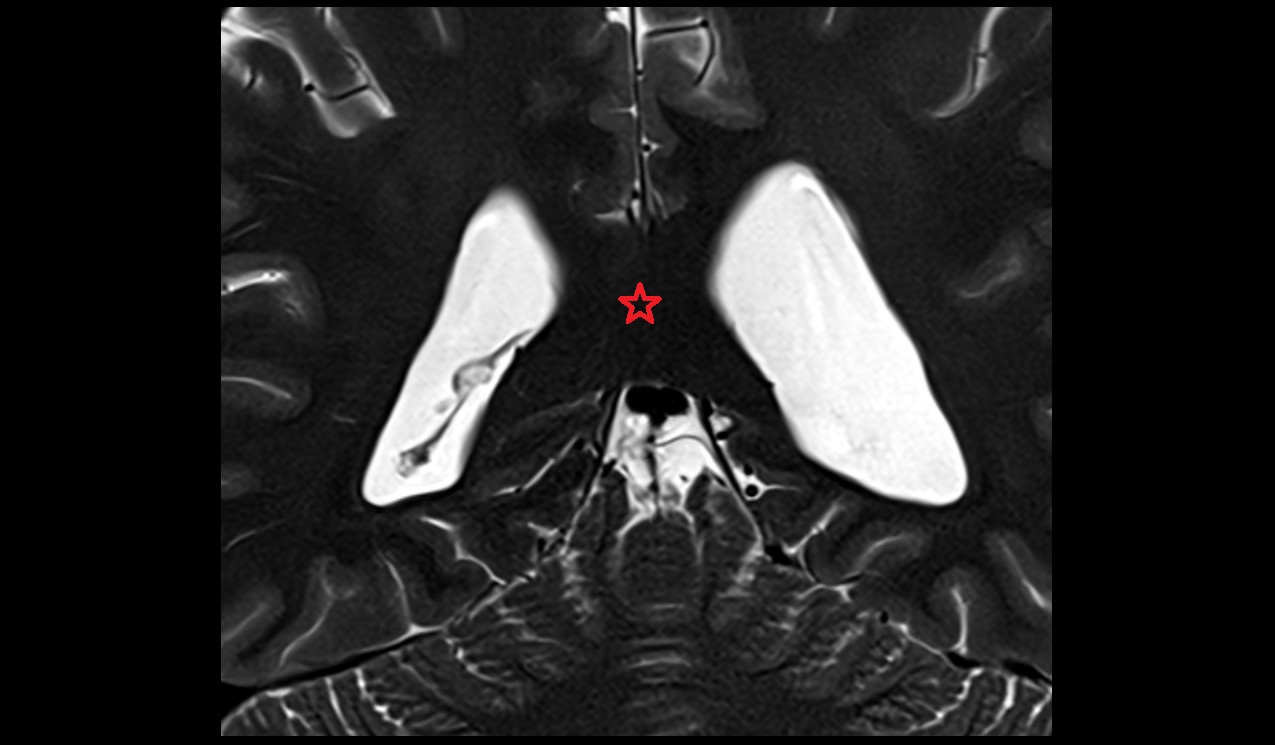

- Seminal vesicle

- Peripheral zone of prostate

- Anterior Fibromuscular Stroma of prostate

- Central zone of prostate

- Transitional zone of prostate

- Urinary bladder

- Rectum